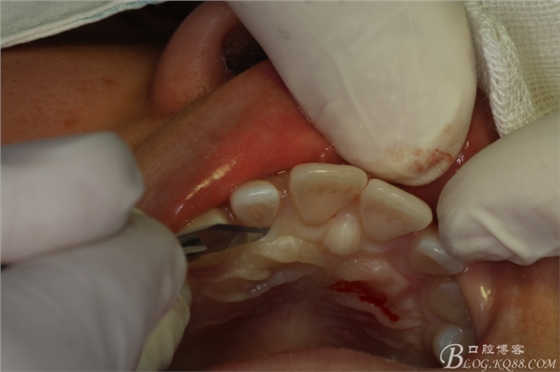

圖5.唇、腭側(cè)局部無痛浸潤麻醉

圖6.行腭側(cè)齦溝內(nèi)水平切口。